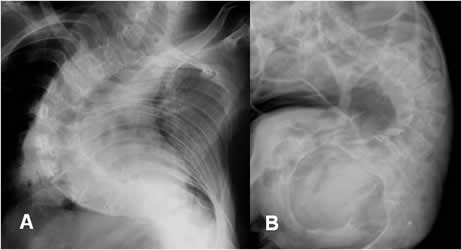

Fig 43. Escoliosis severa.

A y B: Rx AP. Severas rotoescoliosis dorsolumbares, en pacientes con parálisis cerebral, donde estaría indicado el manejo quirúrgico.